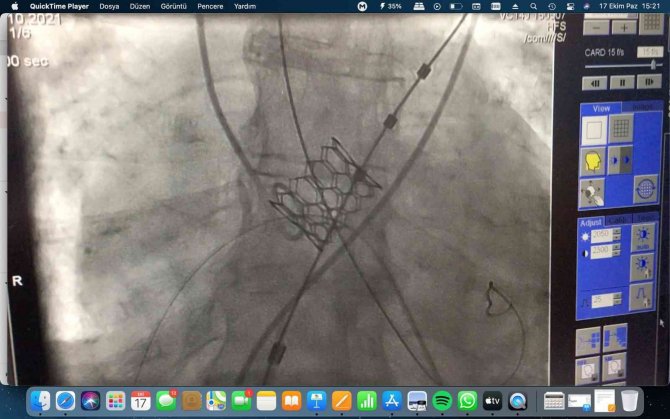

Kütahya Evliya Çelebi Eğitim ve Araştırma Hastanesi'ne başvuran ve aort kapağında ciddi darlık olan 88 yaşındaki hastanın, aort kapağı ameliyat edilmeden başarıyla değiştirildi.

Ameliyat riski yüksek olan hastanın aort kapağı, KSBÜ Kardiyoloji ile Kalp ve Damar Cerrahisi hekimlerinin ortak işlemi ile göğüs duvarı açılmadan, ameliyatsız bir şekilde kasıktan yapılan bir işlem ile başarılı bir şekilde değiştirildi.